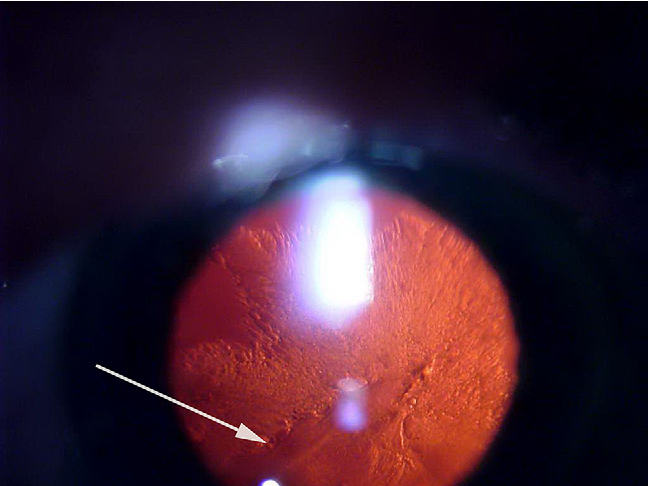

전방에 염증세포들과, 방수흐림(AC flare)이 관찰되고,

전방에 흰물질 덩어리가 관찰됩니다.

염증이 지속되면 홍채후유착이나, 주변부홍채유착등도 관찰될수 있습니다.